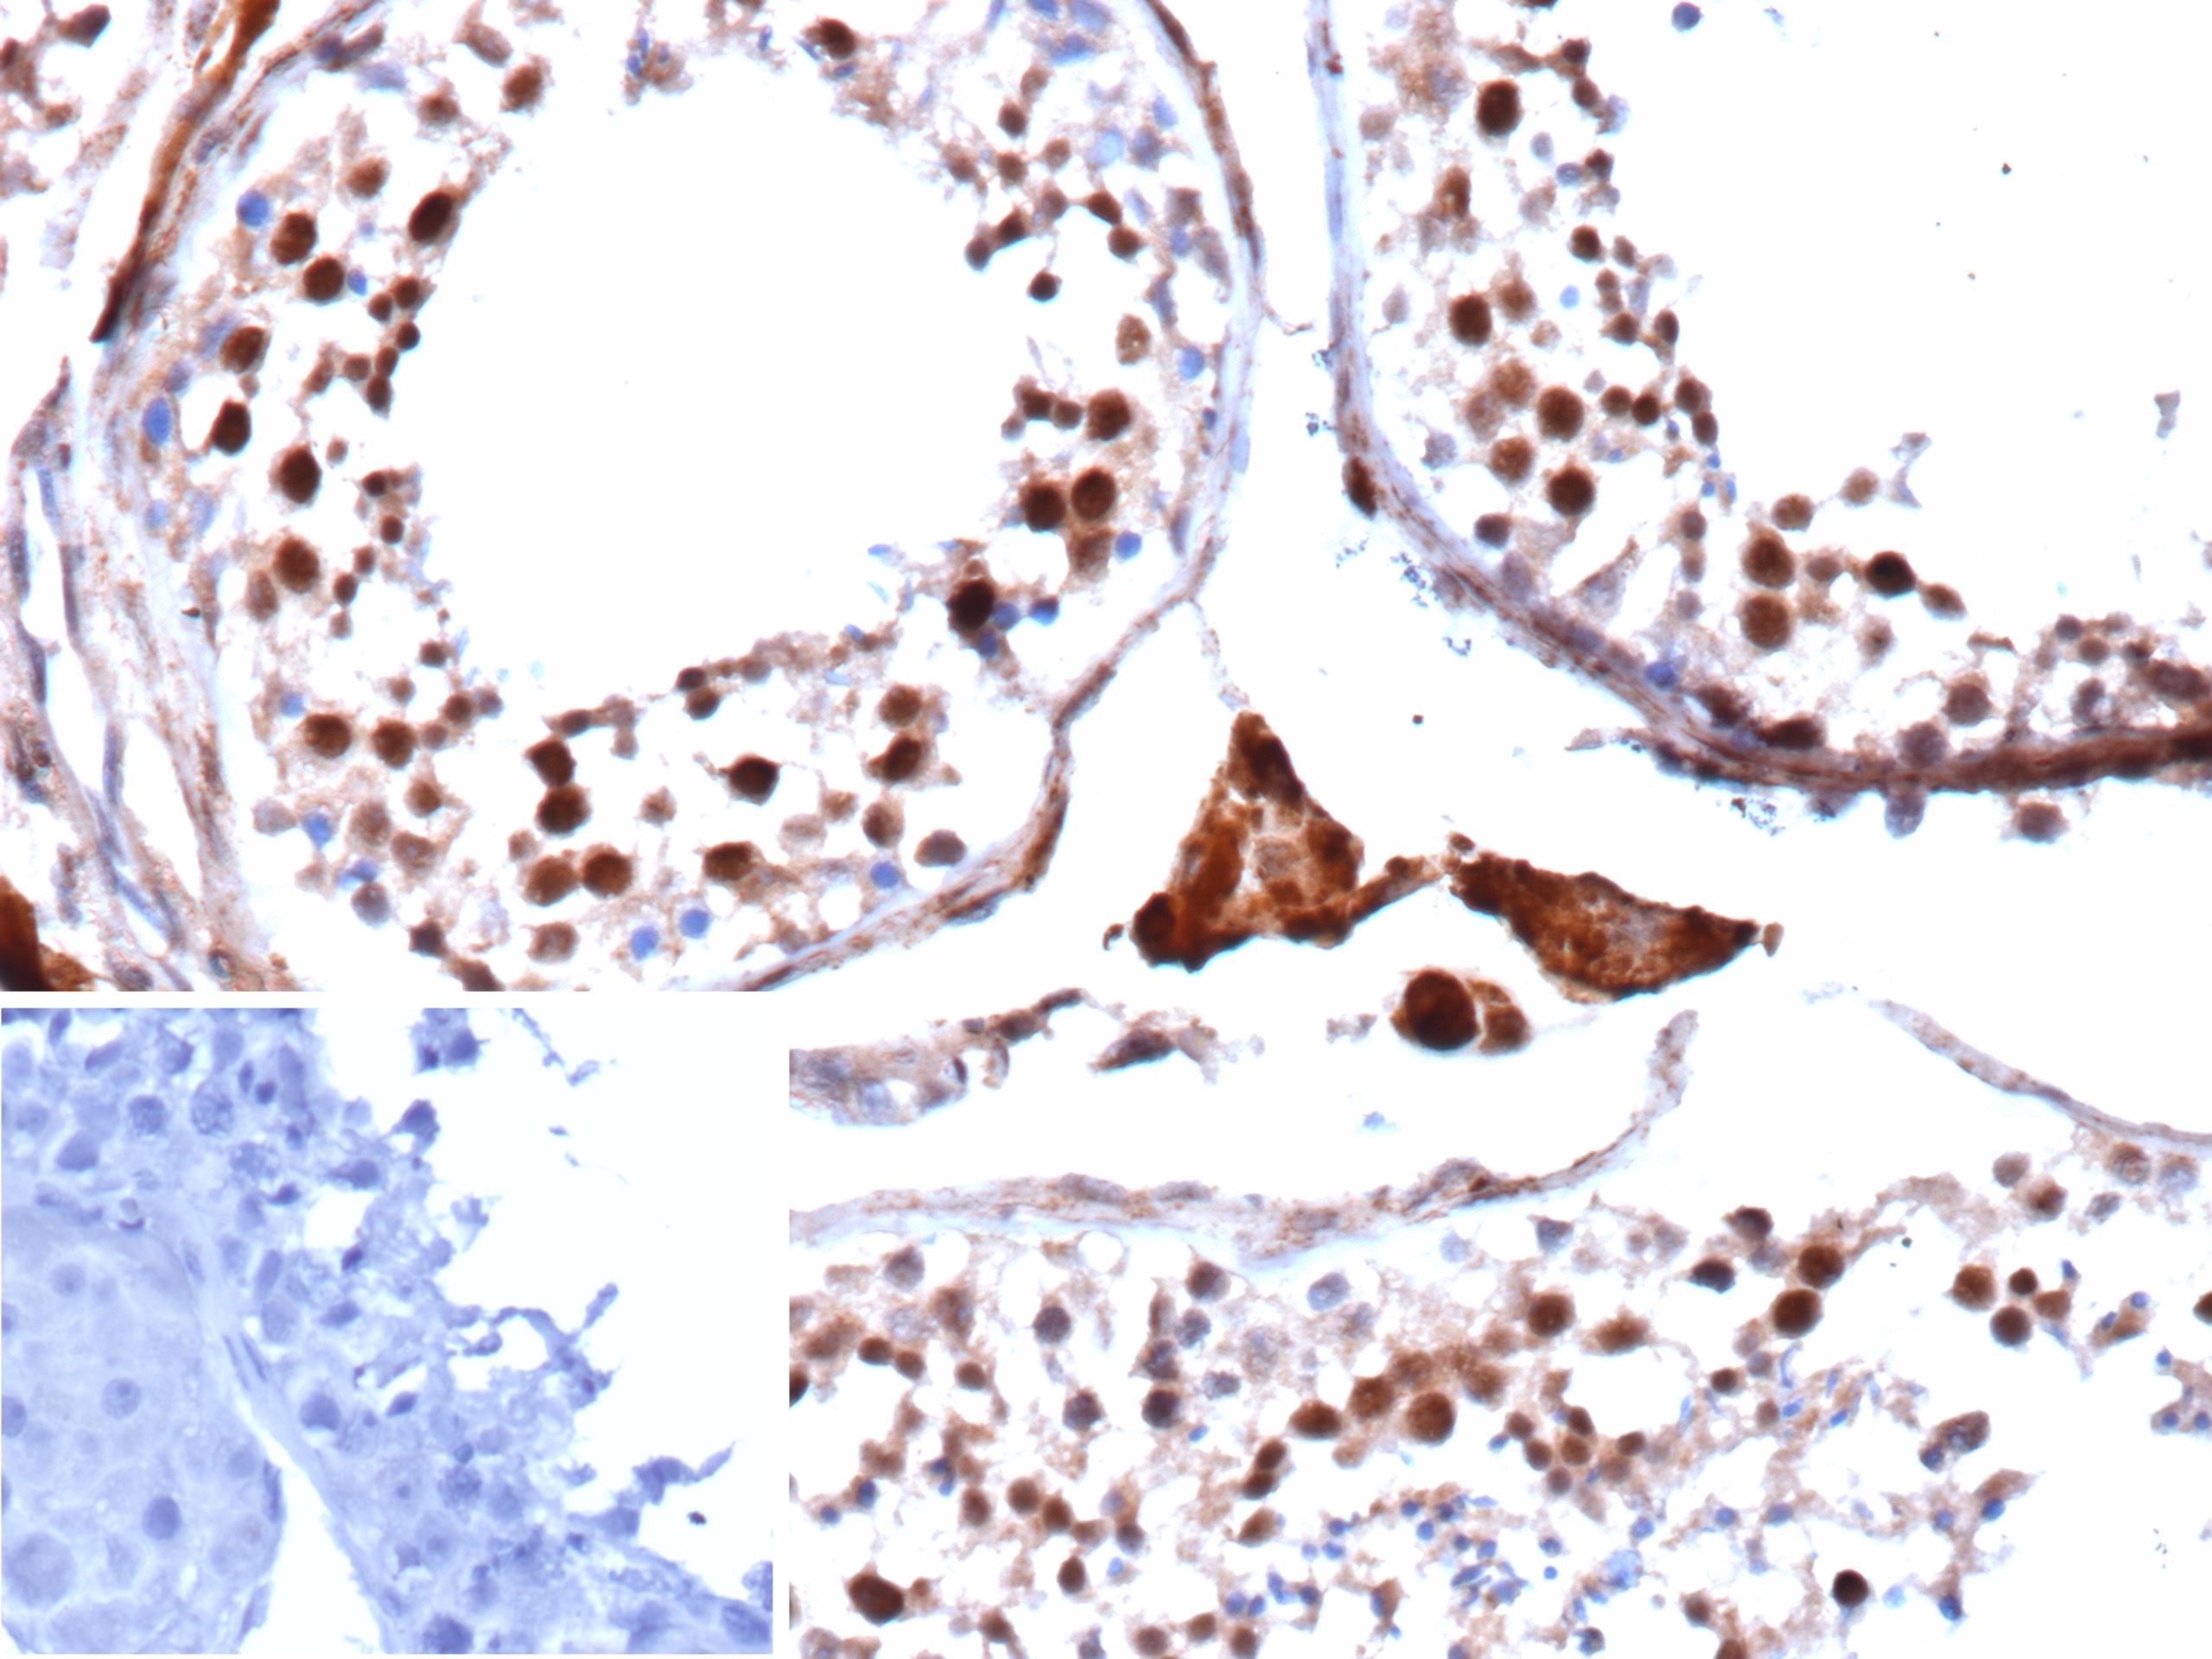

Immunohistochemistry (IHC)

1-2ug/ml

30 min at RT. Staining of formalin-fixed tissues requires heating tissue sections in 10mM Tris with 1mM EDTA, pH 9.0, for 45 min at 95°C followed by cooling at RT for 20 minutes

It recognizes a transcription factor of 64-67kDa, identified as c-myc. Its epitope spans between aa 410-419 (EQKLISEEDL) which is a specific portion of an alpha helical region of human c-myc protein. This MAb shows no cross-reaction with v-myc. c-myc is involved in the control of cell proliferation and differentiation and is amplified and/or overexpressed in a variety of tumors. Over-expression of c-myc protein occurs frequently in luminal cells of prostate intraepithelial neoplasia as well as in most primary carcinomas and metastatic disease. �